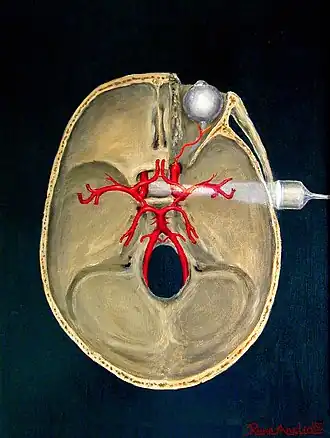

Transcranial Doppler insonation of the cerebral circulation

Transcranial Doppler (TCD) and transcranial colour Doppler (TCCD) measure the velocity of blood flow through the brain's blood vessels transcranially (through the cranium). These modes of medical imaging conduct a spectral analysis of the acoustic signals they receive and can therefore be classified as methods of active acoustocerebrography. They are used as tests to help diagnose emboli, stenosis, vasospasm from a subarachnoid hemorrhage (bleeding from a ruptured aneurysm), and other problems. These relatively quick and inexpensive tests are growing in popularity. The tests are effective for detecting sickle cell disease, ischemic cerebrovascular disease, subarachnoid hemorrhage, arteriovenous malformations, and cerebral circulatory arrest. The tests are possibly useful for perioperative monitoring and meningeal infection.[7] The equipment used for these tests is becoming increasingly portable, making it possible for a clinician to travel to a hospital, to a doctor's office, or to a nursing home for both inpatient and outpatient studies. The tests are often used in conjunction with other tests such as MRI, MRA, carotid duplex ultrasound and CT scans. The tests are also used for research in cognitive neuroscience.